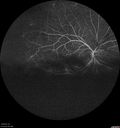

Grade 4 hypertensive retinopathy444 views55 year old man Hhe did have headaches a few weeks ago and also some nausea and vomiting. He noticed for a few weeks the vision in the left eye was blurred and that the vision in the left eye is dark.

VA OD: Dcc20/20

VA OS: Dcc20/100-1

He was admitted directly to ICU for blood pressure control (290 / 170 mmHg)

3 weeks later his VA increased to 20/20 OD, 20/32 OSJan 29, 2019